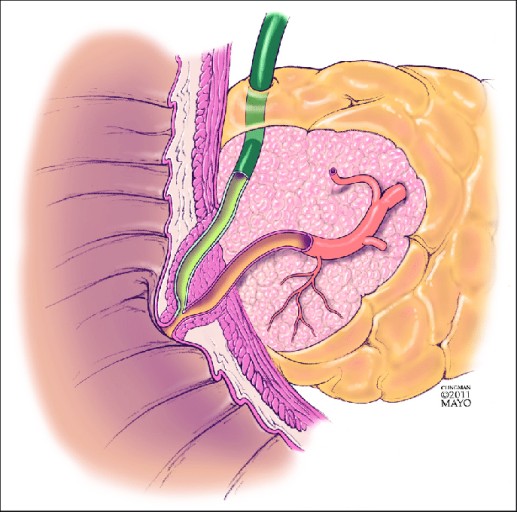

- 위장이나 담도, 십이지장을 눌러서 음식물이 장으로 잘 내려가지 않게 되면서 생깁니다.

- 명확한 이유 없이 반복되는 메스꺼움이나 구토는 반드시 소화기내과 진료가 필요해요.